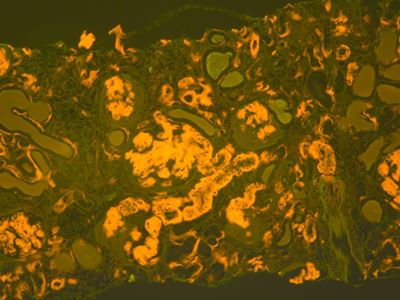

Amyloidosis is a rare but serious disease caused by the buildup of abnormal amyloid deposits in the body. The new guideline aims to support earlier and more accurate diagnosis, which is critical for effective treatment but has often been challenging for laboratories and pathologists.

• Congo Red Stain: Remains the standard for amyloid detection; other stains should be validated.

• Fluorescence Microscopy: May improve Congo red sensitivity where available.